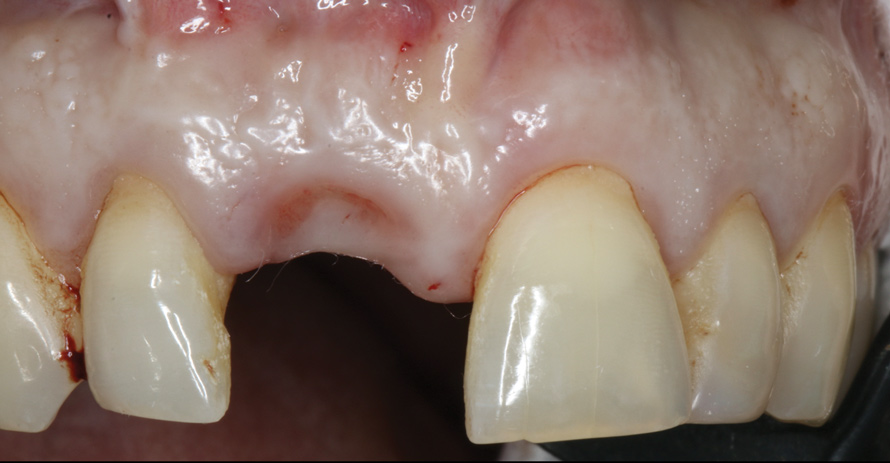

4. Facial and occlusal views of initial clinical presentation of tooth No. 8.

Figure 4

5. Facial and occlusal views of initial clinical presentation of tooth No. 8.

Figure 5

A 56-year-old female patient was referred for the evaluation of tooth No. 8 (Figure 4 and Figure 5). A periapical radiograph indicated that the tooth had undergone apicoectomy and received an excessively long post (Figure 6), and a cone-beam computed tomography (CBCT) scan of the site revealed a lack of buccal plate bone (Figure 7).

Esthetic implant placement was selected as the preferred treatment modality to restore function, preserve the smile, and provide a psychologic benefit. In addition to performing a complete periodontal evaluation, including periodontal probing, localization of the gingival margin, and calculation of the clinical attachment level, it was necessary to quantify the amount of keratinized tissue and gingival thickness for diagnosis and treatment planning. This patient was diagnosed with localized periodontitis (Stage II, Grade B) as well as other conditions affecting the periodontium, including an endodontic-periodontal lesion and gingival recession.26